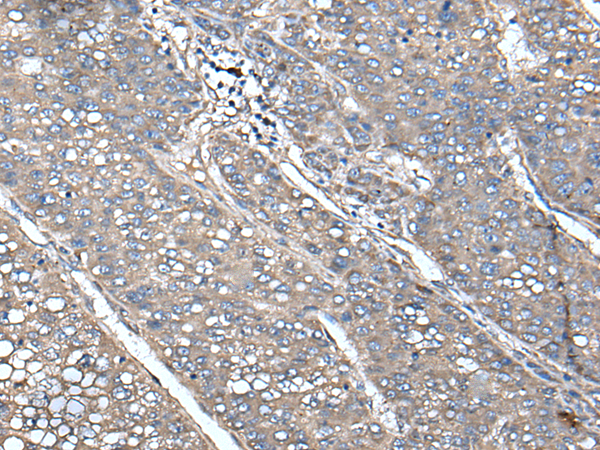

IHC positive control: |

Human liver cancer and Human lung cancer |